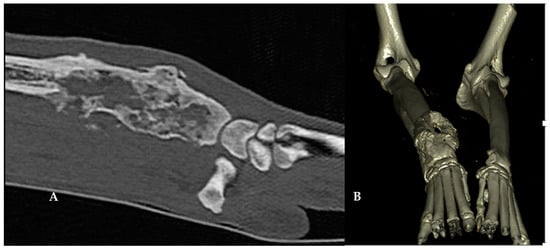

2.4. Cementoplasty

3. Results